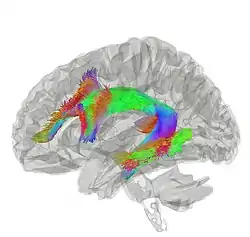

Tractography showing arcuate fasciculus | |

In neuroanatomy, the arcuate fasciculus (AF; from Latin 'curved bundle') is a bundle of axons that generally connects the Broca's area and the Wernicke's area in the brain. It is an association fiber tract connecting caudal temporal cortex and inferior frontal lobe.[1]

The arcuate fasciculus is a white matter tract that runs parallel to the superior longitudinal fasciculus. Due to their proximity, some researchers refer to them interchangeably. They can be distinguished by the location and function of their endpoints in the frontal cortex. The arcuate fasciculus terminates in Broca's area (specifically BA 44) which is linked to processing complex syntax. However, the superior longitudinal fasciculus ends in the premotor cortex which is implicated in acoustic-motor mapping.[2]

Historically, the arcuate fasciculus has been understood to connect two important areas for language use: Broca's area in the inferior frontal gyrus and Wernicke's area in the posterior superior temporal gyrus. The majority of scientists consider this to be an oversimplification; however, this model is still utilized because a satisfactory replacement has not been developed.[3] The topographical relationships between independent measures of white matter and gray matter integrity suggest that rich developmental or environmental interactions influence brain structure and function. The presence and strength of such associations may elucidate pathophysiological processes influencing systems such as language and motor planning.

As the technique of diffusion MRI has improved, this has become a testable hypothesis. Research indicates more diffuse termination of the fibers of the arcuate than previously thought. While the main caudal source of the fiber tract appears to be posterior superior temporal cortex, the rostral terminations are mostly in premotor cortex, part of Brodmann area 44.[4][5][6]